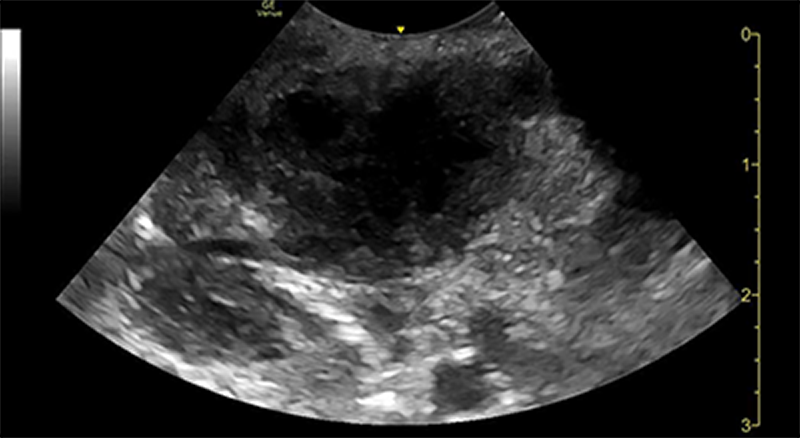

Pus Club

These champions have dominated a peritonsilar abscess!